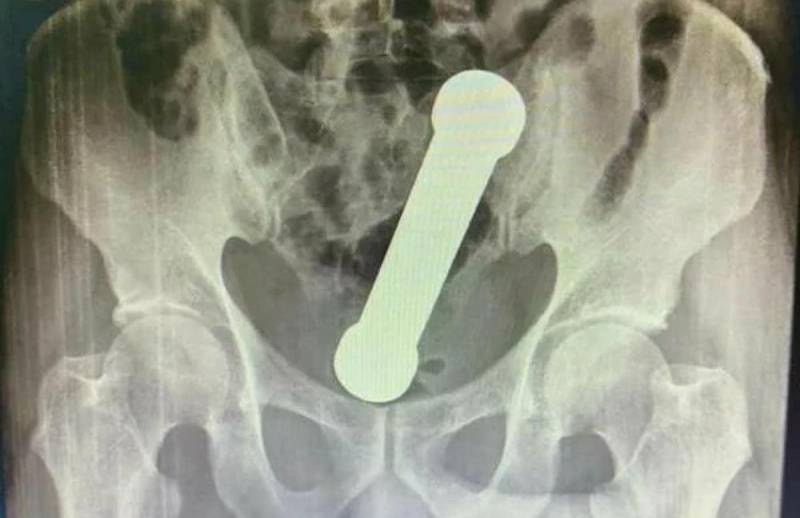

Quando um exame de raio-X foi realizado para a descoberta do problema, foi encontrado um peso de dois quilos dentro do homem.

O objetivo possuía cerca de 20 centímetros de comprimento, da mesma forma dos que são utilizados nas academias de ginástica em exercícios para o braço.

O objeto dentro do homem – um haltere – se encontrava entre o reto e o intestino grosso do paciente. Após o exame, o homem assumiu que teria introduzido o peso de academia no corpo com o objetivo de sentir satisfação sexual.